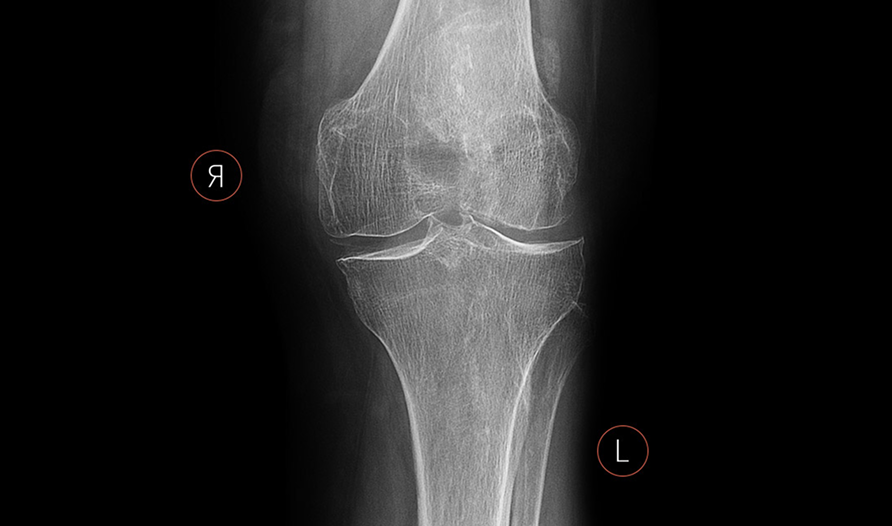

Case study

Marker Detection at a Copenhagen Hospital

The numbers

1 in 5

Of cases, Quality Management staff was alerted of laterality marker inconsistencies

17.7%

Of cases, no markers were used

2.5%

Of cases, incorrect markers were used.

Background

RBmarker™ was rolled out at a large teaching hospital in the Danish capital, Copenhagen. This information empowered staff to look at innovative ways they could improve compliance to agreed protocols and reduce the amount of errors detected in their practice.